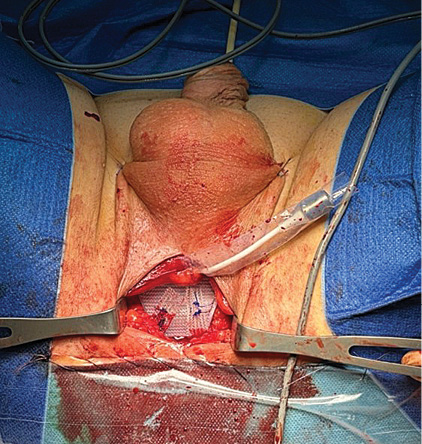

Pacientas ištirtas: atliktas kosulio testas, šlapimo sulaikymo testas, šlapimo tyrimai, urogenitalinės sistemos echoskopija, liekamasis šlapimas, urofloumetrograma, uretrocistoskopija, pilvo ir dubens organų kompiuterinė tomografija. Tyrimų rezultatai parodė, kad nėra infekcijos, šlaplės striktūrų ir liekamojo šlapimo, PSA (prostatos specifinis antigenas serume) tyrimo rezultatas – 0,01 ng/ml, onkologinio proceso plitimo nerasta. Uretrocistoskopijos metu nustatyta, kad sfinkterio vieta neužsidaro, repozicinis testas teigiamas. Įvertinus tyrimų rezultatus ir nustačius vidutinio laipsnio šlapimo nelaikymą, 2023-03-25 pacientui implantuota reguliuojamoji ATOMS sistema (1 pav.).

ATOMS sistema turi dvi dalis: pagalvėlę ir specialų rezervuarą, pagamintą iš titano. Šios dvi dalys tarpusavyje sujungtos. Operacijos metu atliekamas tik vienas pjūvis. Implanto pagalvėlė, duriant specialiomis adatomis, per tarpvietės pjūvį ir per užtvarinę angą pakišama po šlaple. Rezervuaras punktuojamas specialia adata (port needle 20 G/0,9 mm), pagalvėlė užpildoma fiziologiniu tirpalu, kuris patenka į implanto pagalvėlę, esančią po šlaple, ir pagalvėlė priglunda prie šlaplės. Rezervuaras implantuojamas po kapšelio oda. Pagalvėlės pripildymą galima reguliuoti tiek operacijos metu, tiek atlikus operaciją. Reguliuojant šią sistemą po operacijos, chirurginės intervencijos nereikia. Pakanka punktuoti specialia adata per kapšelio odą rezervuarą ir suleisti arba išsiurbti reikiamą skysčio kiekį [8, 9].

Operacija atlikta taikant bendrąją nejautrą, specialiomis adatomis per užtvarinę angą implantuojant pošlaplinio raiščio pagalvėlę po šlaple ir rezervuarą po kapšelio oda (2–5 pav.). Operacija praėjo be komplikacijų.

2 pav. Pošlaplinis implantas

3 pav. Implantas ir rezervuaras

4 pav. Implanto užpildymas punktuojant specialia adata

5 pav. Po kapšelio oda užčiuopiamas rezervuaras